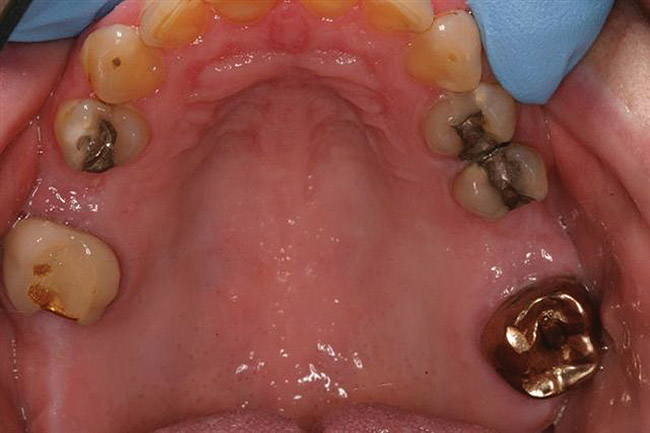

For those extensive restorative cases where a diagnostic and/or treatment wax-up is fabricated (Figure 17 and Figure 18 ), this same technique can be used to create a matrix for sectional provisionalization of the patient. The TempTray and Template are used to impress the mock-up (Figure 19), removed (Figure 20), loaded with bis-acryl, and re-inserted over the prepared teeth to create a provisional that needs little contouring and finishing ( Figure 20 and Figure 21). After application of the glaze (Figure 23), the temporary is inserted with temporary cement, the excess removed, and the occlusion verified (Figure 24).

Figure  19  The mock-up is impressed,removed, loaded with bis-acryl, and re-inserted over the prepared teeth to create a provisional that needs little contouring and finishing.

Figure 19

Figure 20 The mock-up is impressed,removed, loaded with bis-acryl, and re-inserted over the prepared teeth to create a provisional that needs little contouring and finishing.

Figure 20

Figure 21  The mock-up is impressed,removed, loaded with bis-acryl, and re-inserted over the prepared teeth to create a provisional that needs little contouring and finishing.

Figure 21

Figure 22 The mock-up is impressed,removed, loaded with bis-acryl, and re-inserted over the prepared teeth to create a provisional that needs little contouring and finishing.

Figure 22